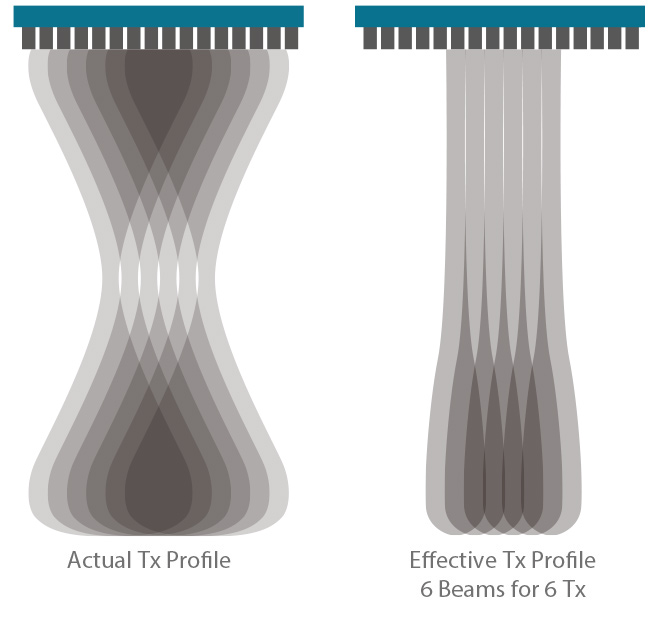

Enfoque de zona

La plataforma ZST+ realizó el enfoque de zona en todo el campo de visión con tecnología de enfoque dinámico de píxeles, asegurando que las imágenes desde la piel superficial hasta la profundidad Los órganos de cualquier animal están en el estado de enfoque en tiempo real.

Enfoque dinámico de píxeles basado

En ZONE Sonography™

Tecnología ZONE Sonography™+